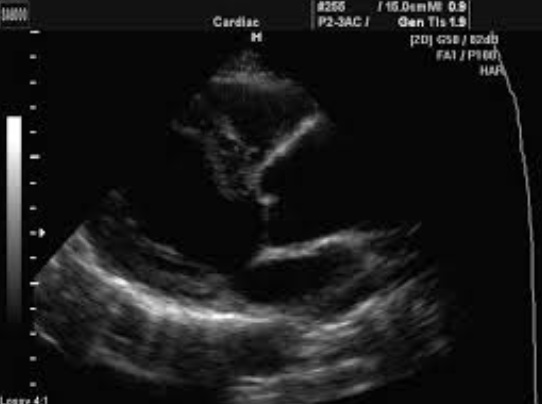

ЕХОКГ

Ехокардіографія